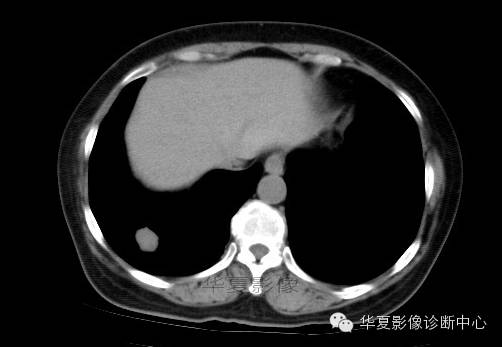

影像资料:

术中切除(右下)部分肺组织7x6x2cm,切面见一灰白色肿物,直径2cm,质较脆,与周围组织界限清,略呈分叶状,无包膜。

(右下肺)错构瘤(以软骨成份为主)

肺错构瘤多发生在胸膜下肺表浅部位,呈球形、椭圆形,有完整的包膜,质硬,易与周围肺组织分开。肺错构瘤的直径0.5~12cm,多数小于3cm。肿瘤剖面呈灰白色,质硬,有黏液和囊腔。主要成分有软骨、腺体、平滑肌、脂肪及纤维组织等。肿瘤可发生钙化,多位于中心,分布较均匀,此种钙化结构常像爆米花样或核桃肉样。